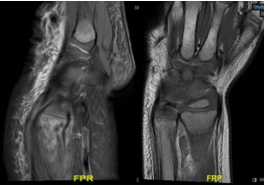

The radiographs bilateral ulnar symmetrical distal metaphyseal eccentric osteolytic lesions are seen with disruption of the medial cortex; however no periosteal reaction. Also, there is small osteolytic lesion within the distal radius (Figure 2). Both knees showed signs of osteopenia, the thick sclerotic metaphyseal line above a widened physis, and small beak-like excrescences at the metaphysis of both tibias (metaphyseal clefts). Ring of increased density surrounding epiphysis (Wimberger ring) (Figure 3). US guided aspiration of both knees show no signs of infection. MRI of wrist was done which show diffuse bilateral bone marrow oedema of the distal ulna and radius both sides. This is associated with evidence of diffuse periosteitis and soft tissue oedema however no apparent fluid collections. Subcutaneous oedema is also identified. No apparent acute fractures. No focal osseous lesions. Intact extensor and the flexor tendons bilaterally and bone: Generalized bone marrow oedema is seen more pronounced around the knee and wrist joints. (Figure 4).

Figure 4 MRI of the wrist Diffuse bilateral bone marrow oedema of the distal ulna and radius both sides. This is associated with evidence of diffuse periosteitis and soft tissue oedema.